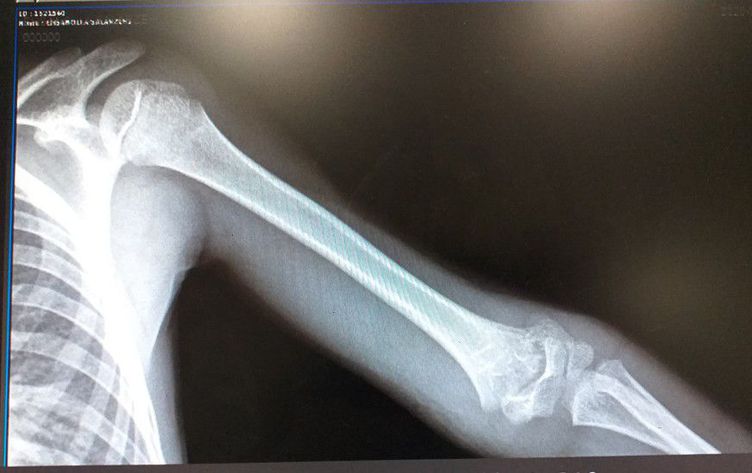

What is your diagnosis?

Supracondilar fracture of humerus